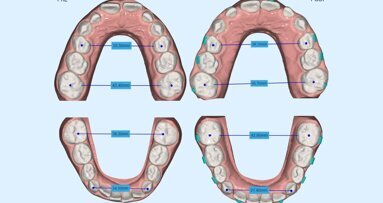

Recentemente sono stati introdotti sul mercato strumenti e materiali che hanno lo scopo di permettere riabilitazioni complete dell’edentulia totale in tempi estremamente ridotti, con elevata predicibilità estetica e funzionale. La scansione intraorale delle arcate complete consente di avere immediatamente a disposizione la morfologia dei processi alveolari nell’intercuspidazione abituale del paziente. Grazie a software di ultima generazione è possibile rimuovere virtualmente gli elementi dentali residui.

L’assiografia digitale associata a DICOM 3D offre una valutazione reale delle determinanti condilari e una simulazione dei movimenti masticatori. Un software di ricostruzione 3D in pochi minuti consente la ricostruzione completa delle arcate con protesi totali con una valutazione accurata del ripristino della dimensione verticale. La ricostruzione del profilo estetico funzionale integrato (via via condiviso nelle simulazioni in prima visita col paziente) diventa reale.

Fig. 4_Scansione intraorale superiore e inferiore.

Fig. 5_La rimozione virtuale della Toronto superiore con software exocad.

Fig. 6_La protesi superiore e inferiore disegnate con le librerie Ivoclar Ivotion.

La protesi totale digitale è un metodo assolutamente predittivo dei tempi di esecuzione. I software di ultima generazione consentono valutazioni assolutamente accurate della congruità delle determinanti occlusali, dei piani di svincolo, della simulazione di movimenti masticatori. Il paziente riceve una soluzione immediata in giornata, dalla bonifica completa alla riabilitazione totale mobile anche di entrambe le arcate.

La soluzione in una singola seduta della protesi totale mobile diventa grazie al metodo della scansione intraorale delle arcate il progetto protesico immediato e il fraseggio con vhf R5 a 5 assi del disco Ivotion Ivoclar Vivadent, proprietario della Shell Geometry. Nella nostra esperienza clinica questo tipo di processo ottimizza tempi e costi nel protocollo di riabilitazione totale in Day Dentistry.